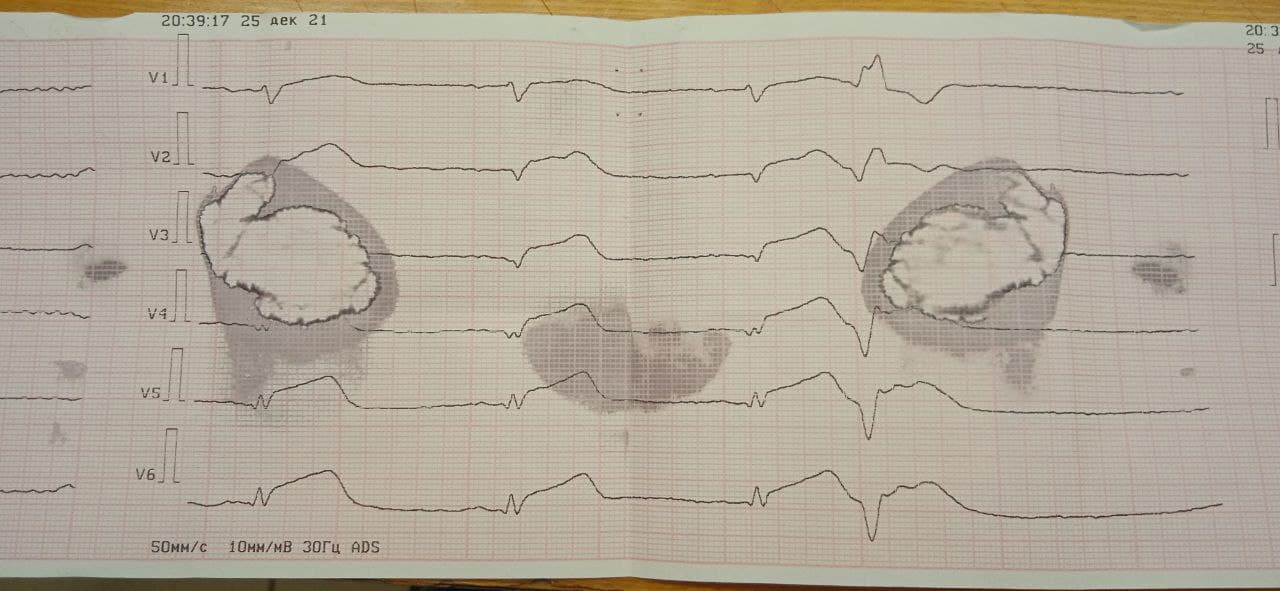

ЭКГ 209: ОКС с подъемом ST. Ранние желудочковые ЭС.

Пациент мужчина 66 лет.